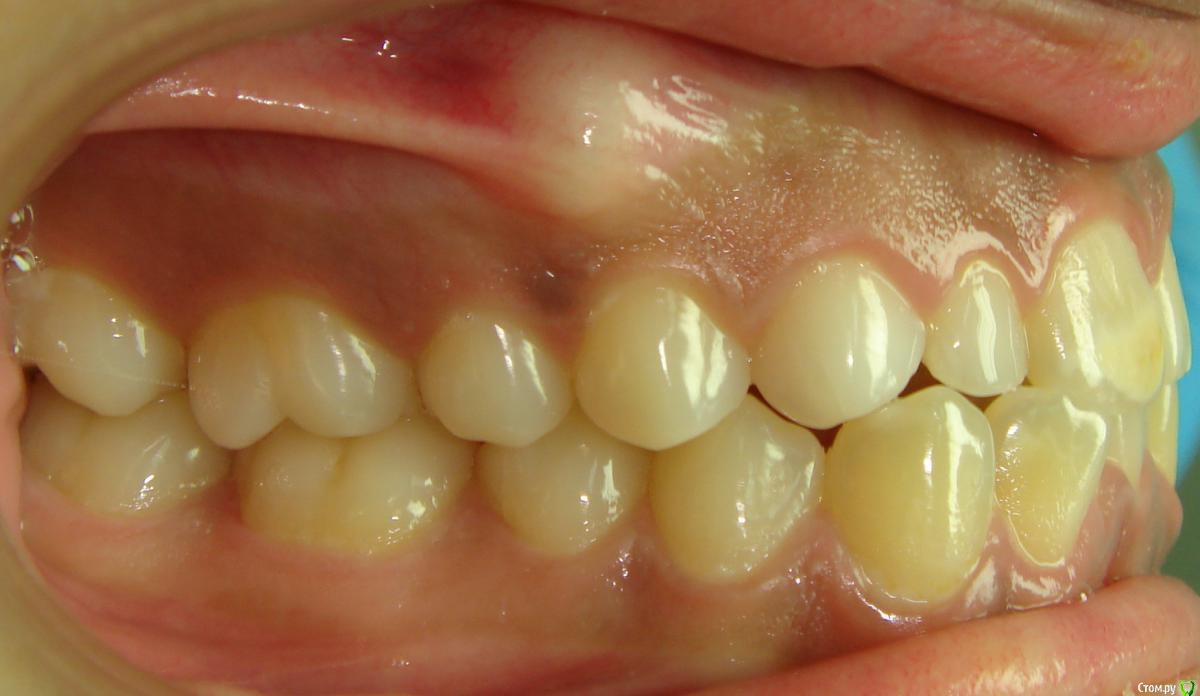

Opdihatop Опубликовано 20 февраля, 2017 Поделиться Опубликовано 20 февраля, 2017 Здравствуйте, коллеги! Вот такой вот случай третьего класса, вертикального роста, множественной первичной адентии и преинтереснейшего 13-го зуба. Девочке 14 лет. Сразу скажу, что вопреки некоторым классикам удалять клык или премоляры мы не будем, будем ставить в дугу, причем на его законное место. Может у кого-то были подобные случаи, поделитесь опытом, будьте добры. Какой план лечения и какая биомеханика тут будут самыми оптимальными? Заранее всем спасибо! Ссылка на комментарий

Opdihatop Опубликовано 20 февраля, 2017 Автор Поделиться Опубликовано 20 февраля, 2017 52, 53 молочные. 12, 22 - адентия. Клык пойдет на место 13. Когда-то на курсе Рафаэля Спены видел подобное, но, к сожалению не зафиксировал на фото. В общем и целом принцип помню. Но тут есть одно огромное НО... 14, 15 началась резорбция верхушек из-за 13 зуба, что видно по КТ. Ссылка на комментарий

Yana guapa Опубликовано 20 февраля, 2017 Поделиться Опубликовано 20 февраля, 2017 у ВАшей девочки я бы удаляла восьмерки, ставила винты в подскуловую область , часть зубов назад, а часть - пружинами вперед. создавая место. про клык - здесь конечно по КТ надо смотреть, куда его тащить и как открывать. Возможно лучше вначале открыть место (раздвинуть 5ку и 4ку) а потом клык поставить между ними. Клык станет 4кой а 4ка клыком. (имхо) 1 Ссылка на комментарий

Opdihatop Опубликовано 20 февраля, 2017 Автор Поделиться Опубликовано 20 февраля, 2017 (изменено) вот такая штучка еще в кости... Видел, на вид - простая остеомка, так что пугать пациента не буду, передвижению зубов не мешает. а про каких именно классиков Вы говорите? (это я для себя, для развития..) Вот простите, не вспомню, читал монографию какого-то итальянца еще на этапе обучения, так там было сказано вообще их удалять, особенно при транспозиции через ц.л. у ВАшей девочки я бы удаляла восьмерки, ставила винты в подскуловую область , часть зубов назад, а часть - пружинами вперед. создавая место. про клык - здесь конечно по КТ надо смотреть, куда его тащить и как открывать. Возможно лучше вначале открыть место (раздвинуть 5ку и 4ку) а потом клык поставить между ними. Клык станет 4кой а 4ка клыком. (имхо) Подскуловые импланты, это классно, только вот в Украине этих корейцев не продают пока (Диаметра не хватает и длины). Дистализирую пружинами при непрямом анкораже на микроимплантате между 5 и 6. Как я собирался тянуть клык вперед? На 14, 15 ставятся брекеты от нижних премоляров и ставятся они на толстую композитную подушку, которая постепенно утолщается. Таким образом зубы постепенно уходят орально, а их корням придается небный торк, освобождая путь в кости для 13. Затем при помощи компактостеотомии быстро мезиализируется 13, затем 14 и 15 плавно перемещаются назад (хотя 15 это вряд ли коснется... его я планирую перед этим дистализировать). Сам я такое не делал, но видел на курсе. Вот, выпал шанс попробовать. Зачем? Во-первых, научный интерес, во-вторых, родители категорически против ремоделирования коронок зубов... Изменено 20 февраля, 2017 пользователем Opdihatop Ссылка на комментарий